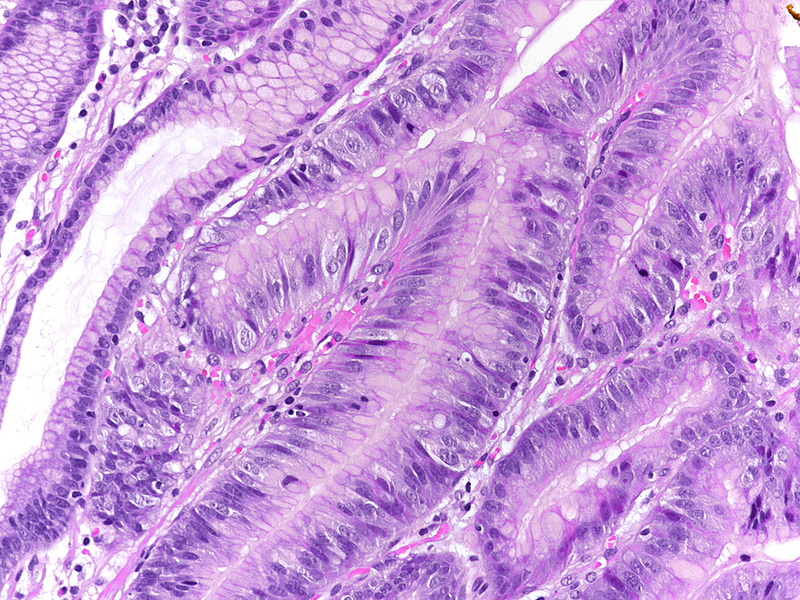

Upon histology, the three polyps showed a similar morphology. The polyps demonstrated irregularly shaped, branching, papillary projections with well-vascularized stroma (Panels A-C). On higher magnification, these projections were lined by dysplastic columnar cells, with hyperchromatic, enlarged and stratified nuclei and a distinctive apical mucin cap, prompting diagnosis of foveolar-type gastric adenoma with low-grade dysplasia (Panels D-F). The background tissue showed non-atrophic oxyntic mucosa, without gastritis, Helicobacter pylori infection or intestinal metaplasia. In summary, the histology was consistent with the newly described variant of foveolar-type adenoma with a raspberry-like appearance.